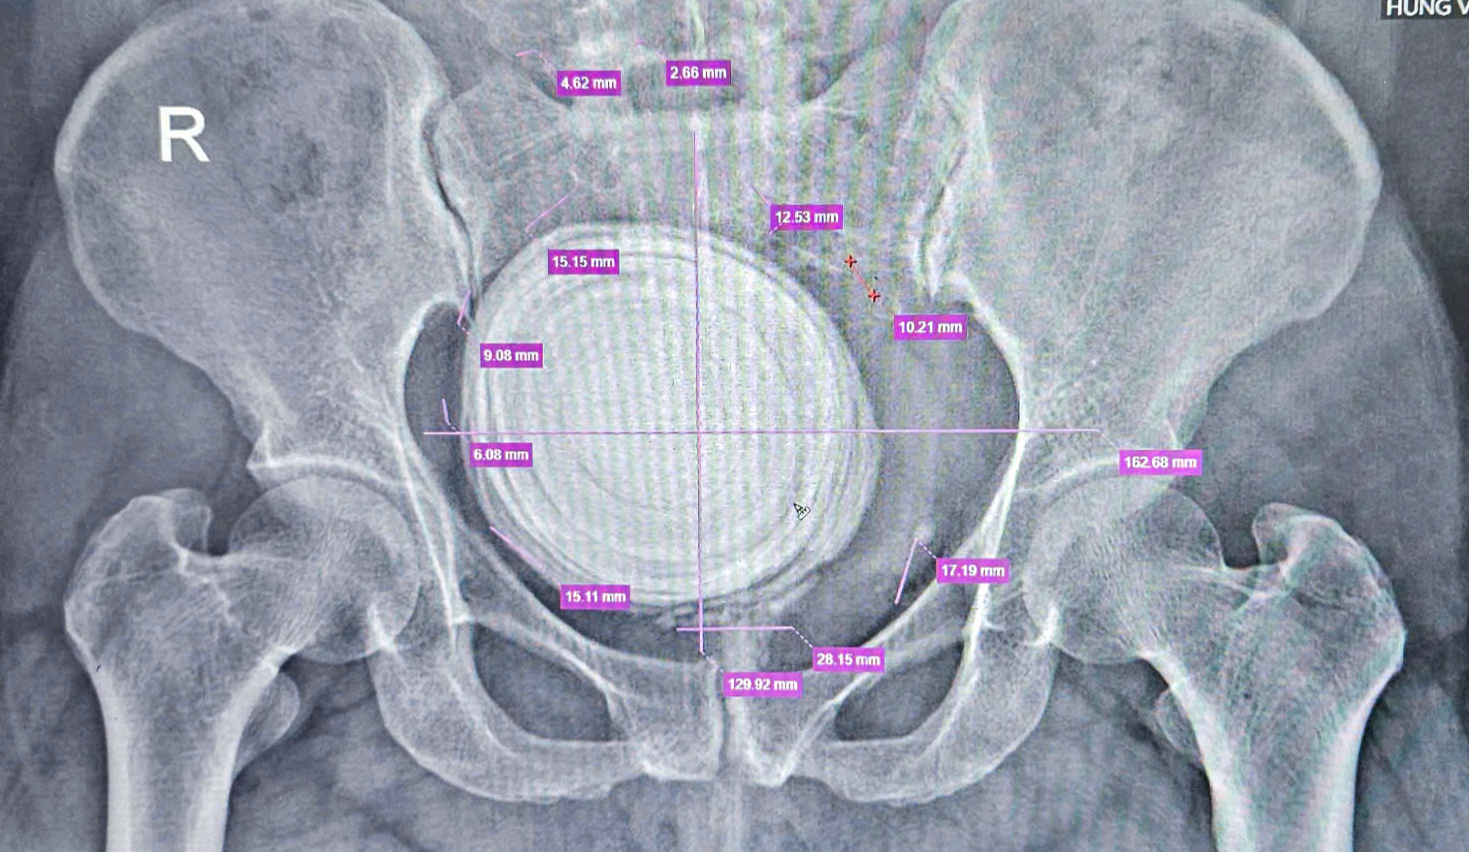

ภาพเอกซเรย์แสดงให้เห็นนิ่วขนาดใหญ่ที่เกือบจะครอบคลุมกระเพาะปัสสาวะทั้งหมดของผู้ป่วย VTTN - ภาพ: BVCC

หลังจากเอกซเรย์แล้ว แพทย์พบว่าผู้ป่วยมีนิ่วขนาดใหญ่อยู่ในกระเพาะปัสสาวะ ซึ่งกินพื้นที่กระเพาะปัสสาวะทั้งหมด ซึ่งอาจก่อให้เกิดความเสียหายต่อเยื่อบุ การติดเชื้อ และการทำงานของระบบทางเดินปัสสาวะบกพร่อง ผู้ป่วยจึงได้รับการผ่าตัดกระเพาะปัสสาวะแบบเปิดเพื่อนำนิ่วออก

แพทย์ได้ผ่าตัดเปิดกระเพาะปัสสาวะของผู้ป่วย และนำนิ่วขนาดใหญ่ออกมา ซึ่งมีความยาวมากกว่า 10 เซนติเมตร ชั้นนอกของนิ่วมีลักษณะนิ่ม โครงสร้างไม่มั่นคง และแตกกระจายเมื่อนำออก แต่แกนของนิ่วค่อนข้างแข็งและกลม